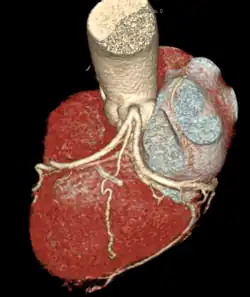

A left S-shaped sinoatrial artery, originating from the proximal left circumflex or LCx artery, has been described as a common variant in approximately 10% of human hearts.[5] This artery is larger than normal and supplies a good part of the left atrium, but also right-sided structures like part of the sinoatrial node and the atrioventricular nodal areas. In this variant, the artery courses in the sulcus between the left superior pulmonary vein and the left atrial appendage where it could be susceptible to injury during catheter or surgical ablation procedures on the left atrium, especially for atrial fibrillation ablation or open-heart cardiac surgery.

Sternocostal surface of heart (right coronary artery visible at left)

Sternocostal surface of heart (right coronary artery visible at left)